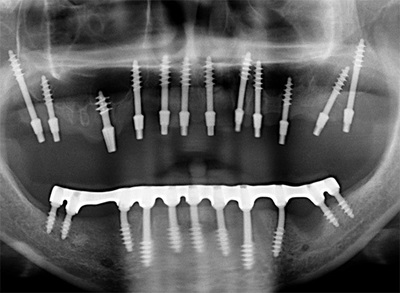

Но мы отвлеклись. Вот снимок пациентки после лечения.

Кроме зубов "мудрости" не удалено ничего. Тут проведено лечение корневых каналов, вкладки, коронки. Какие удаленные 22 зуба? Это бред СМИ, нацеленный на непонятную травлю. Конечно, кого заинтересует новость "пациентке не понравился результат лечения и она подала в суд", фу, уныло. А вот "шок!!врачи-убийцы рядом!! Схватили, выдрали 22 здоровых зуба!!и вкатали счет на миллион!!не допустим врачебного произвола!!!111" - вот это уже вызывает подрыв у очень многих.